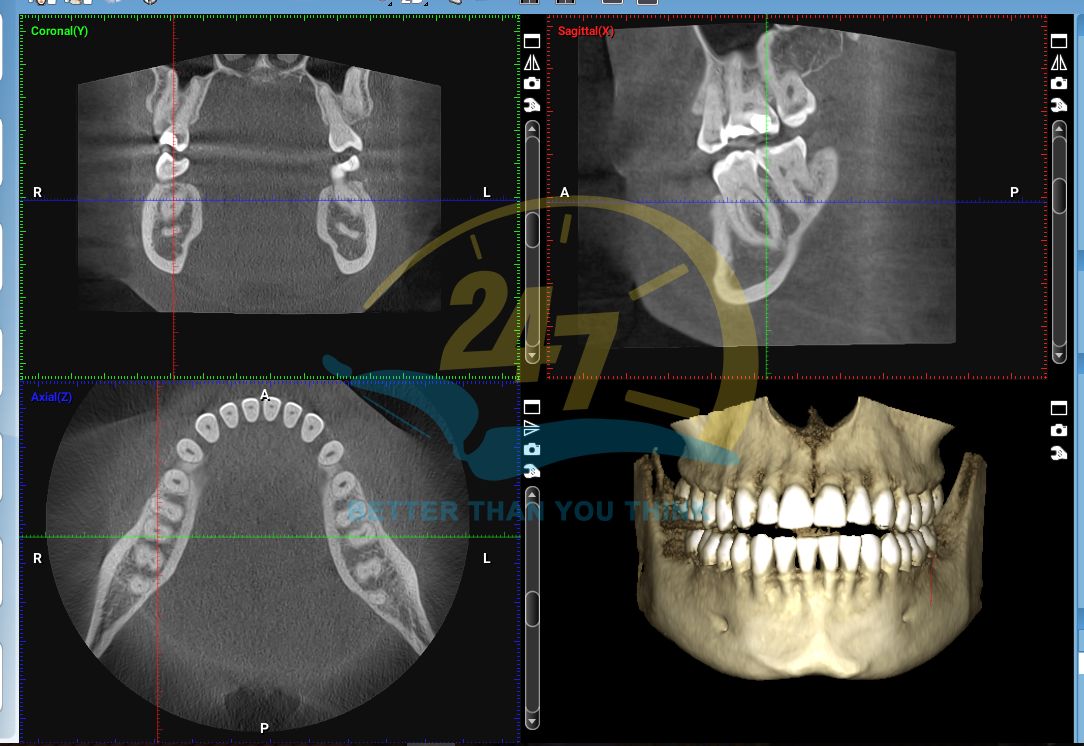

Máy chụp CBCT (Cone Beam Computed Tomography – Chụp cắt lớp vi tính chùm tia hình nón) là một thiết bị chẩn đoán hình ảnh y tế tiên tiến, tạo ra hình ảnh 3D chi tiết của xương, răng, mô mềm và các đường dẫn thần kinh chỉ trong một lần quét.

| Loại hình ảnh | Hình ảnh 3D (không gian ba chiều) | Hình ảnh 2D (phẳng) |

| Mức độ chi tiết | Cung cấp hình ảnh chi tiết, không bị chồng lấp của xương, mô mềm, và các cấu trúc giải phẫu phức tạp. | Hình ảnh có thể bị chồng lấp, hạn chế khả năng quan sát chi tiết các cấu trúc. |

| Ứng dụng | Thường được sử dụng trong các trường hợp phức tạp như lập kế hoạch cấy ghép implant, phẫu thuật răng khôn, chỉnh nha, và chẩn đoán các bệnh lý về xương hàm. | Được sử dụng cho các chẩn đoán thông thường như phát hiện sâu răng, kiểm tra chân răng và các bệnh nha chu. |